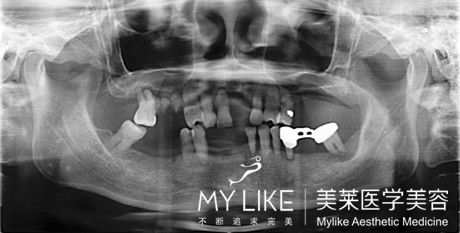

當(dāng)患者全口缺牙或即將拔牙后全口無(wú)牙,佳的處理方案就是進(jìn)行全口種植牙。與傳統(tǒng)的活動(dòng)義齒相比,全口種植牙可以避免牙槽骨漸進(jìn)性萎縮的問(wèn)題,而且種植牙無(wú)異物感,穩(wěn)定舒適,更可恢復(fù)咀嚼功能。

全口種植牙有兩種形式:

1、植入2-3顆牙種植體,起支持和固位的作用,制作全口覆蓋義齒,優(yōu)點(diǎn)是簡(jiǎn)單、便宜。

2、植入4-6顆牙種植體,以種植體支持全口固定烤瓷牙,不需取戴烤瓷牙,舒適方便。 >>>全口牙種植的價(jià)格是多少?